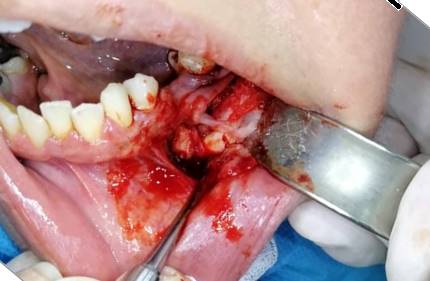

Enucleation of the lesion and curettage with the extraction of the impacted premolar was done intraorally under local anaesthesia. (Figure 4)

Figure 4. Excision of the lesion mass, including the impacted premolar.